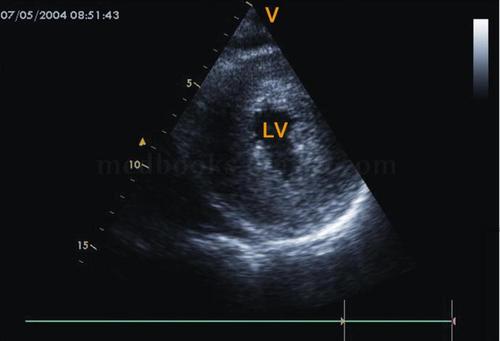

2·m型超声心动图 (1)梗阻者二尖瓣c‐d段呈多层弓背样隆起,称为sam

肥厚型心肌病超声图片

超声心动图